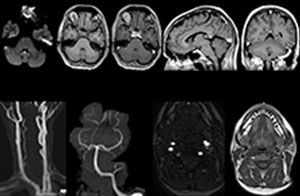

Für Dr. Karis bestehen die nächsten Ziele für die neurologische Notaufnahme in der Umstellung der Untersuchungen für akute Schlaganfall- und TIA-Patienten von CT auf MRT, was eine alternative Managementoption für diese Patienten darstellt. Außerdem wird derzeit die Kooperation mit anderen Abteilungen in die Wege geleitet, was den Nutzen zielgerichteter Untersuchungen mit dem MRT-System in der Notaufnahme noch erhöht. Diese Verbesserungen im Arbeitsablauf können in Kombination mit kürzeren Durchlaufzeiten die Untersuchungsdauer weiter reduzieren.

Klinische Fallbeispiele